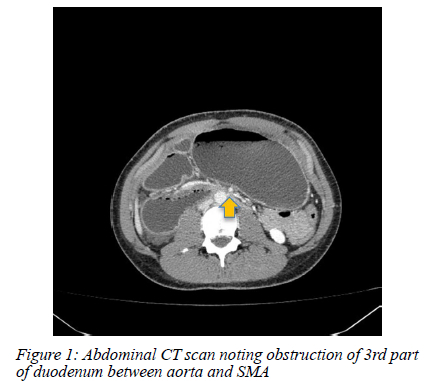

A nasogastric tube was passed and drained 1500 ml of bilious stomach content instantly. The patient was kept nil per mouth, with the nasogastric tube on free drainage, and intravenous fluid was administered. An urgent computer tomography (CT) scan with intravenous contrast was performed as the child was extremely uncomfortable despite analgesia and fluid resuscitation. The CT scan showed an obstruction at the third part of the duodenum with gross stomach and proximal duodenal distension (Figure 1). A clear transition point was seen between the abdominal aorta and superior mesenteric artery (SMA) origin with an aortomesenteric distance of 4 mm and an aortomesenteric angle of 7 degrees (Figure 2).

The CT findings were diagnostic of superior mesenteric artery syndrome (SMAS).

SMAS, otherwise known as Wilkie's syndrome, cast syndrome or chronic duodenal ileus, is a rare cause of upper gastrointestinal obstruction. Characteristically the third part of the duodenum is compressed by the aorta and SMA causing the typical symptoms of early satiety, anorexia, abdominal discomfort or pain, nausea, and vomiting. The normal SMA to aorta angle has been described to range from 38-56 degrees and 10-20 mm in length but in SMAS the angle is decreased ranging from 6-25 degrees and the length 2-8 mm.1'2 The patient had an angle of 7 degrees and 4 mm in length, which is likely why his obstruction was so severe.